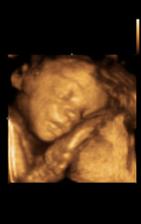

tak to jsou mé první testíky po ivf, je to 9 a 10 den, další testík je 13 den a dnes mi taky bylo potvrzeno těhotenství z krve, hodnota HCG je 678.

Kacatko